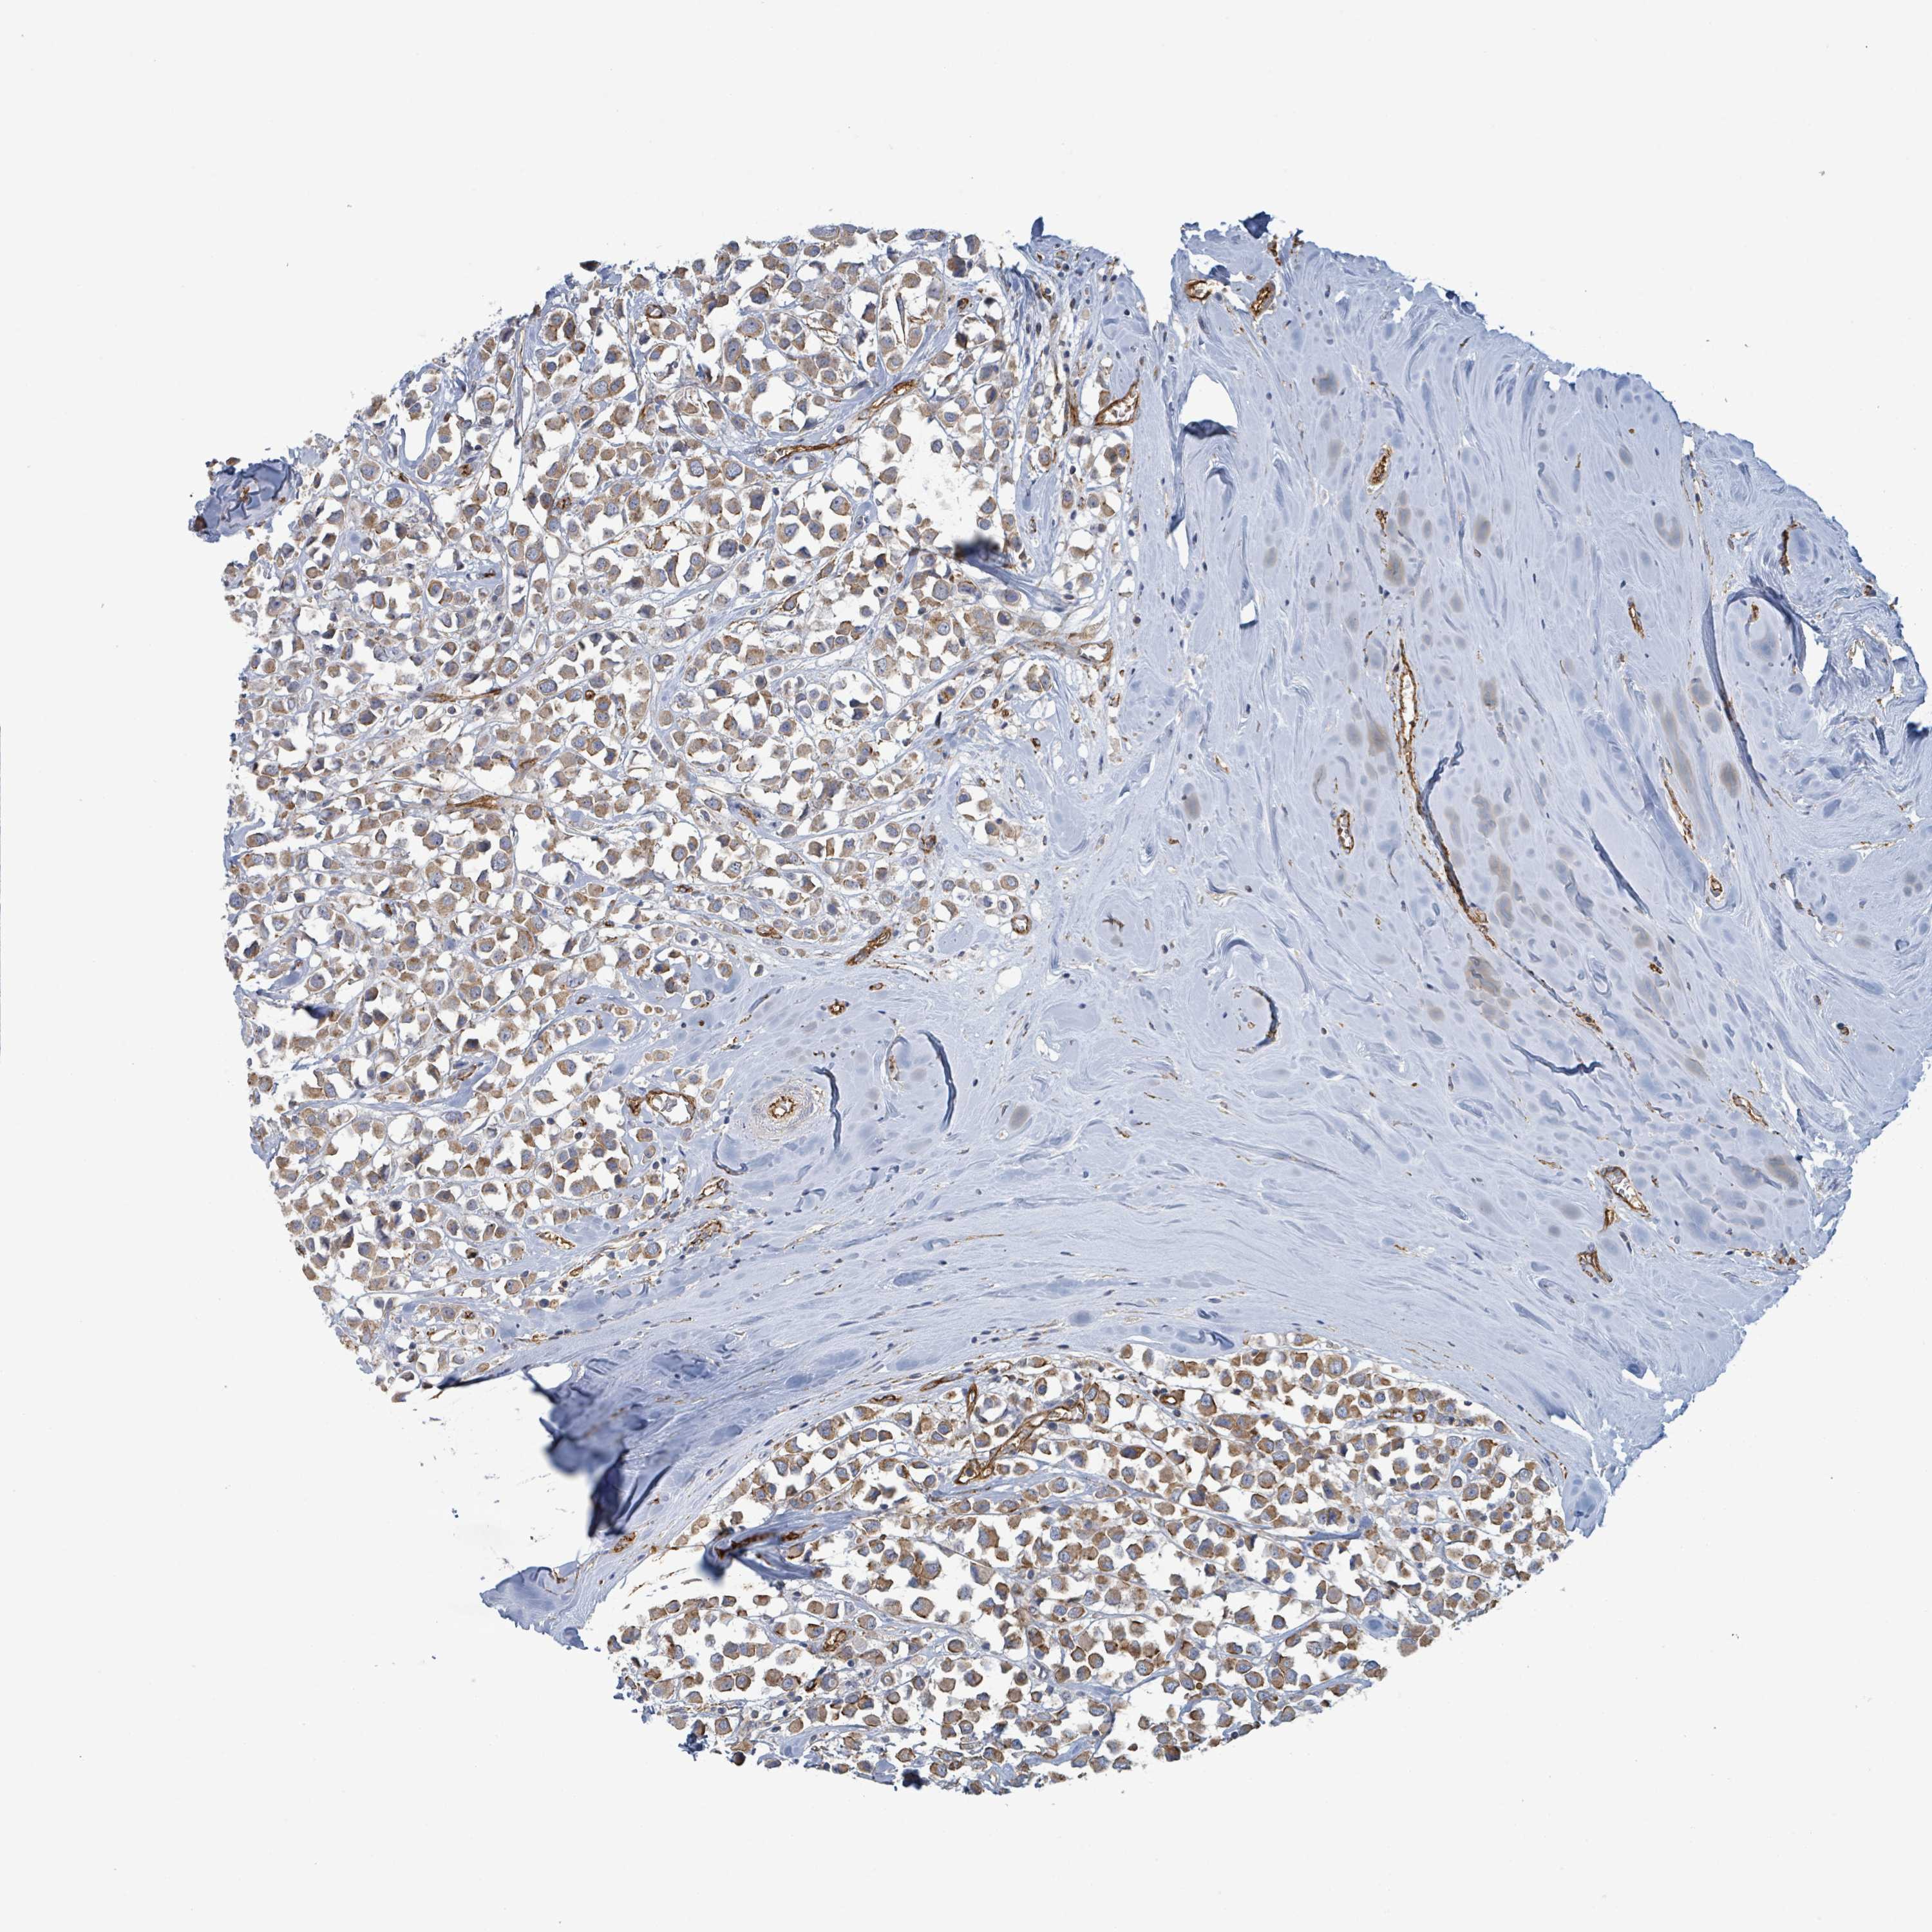

CANCER BREAST CANCER Show tissue menu

BRCA TCGA BRCA VALIDATION PROTEIN EXPRESSION